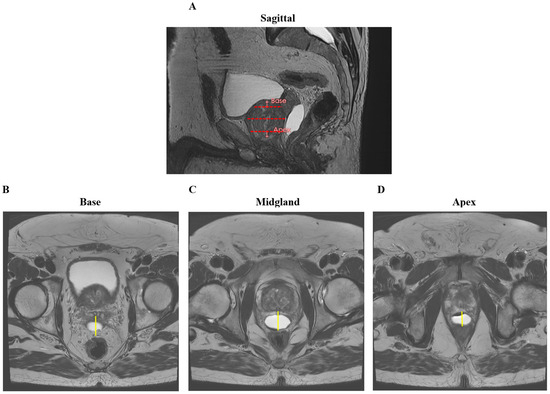

Prostate–Rectum Spacing from Apex to Base and Its Impact on Organs-At-Risk Dosimetry in Prostate Cancer SBRT

Stereotactic body radiation therapy (SBRT) for localized prostate cancer delivers high doses per fraction, making dose constraints for the rectum and other organs at risk critical during treatment planning. This study evaluated the association between prostate–rectum separation, achieved with a biodegradable balloon rectal spacer at different anatomical levels, and corresponding organ-at-risk dose patterns. Thirty-three patients underwent transperineal balloon spacer implantation followed by SBRT to 36.25 Gy in five fractions. Prostate–rectum separation at the apex, mid-gland, and base were measured on CT and/or MRI and categorized as <10 mm, 10–14 mm, or ≥14 mm. Rectal dose–volume parameters and mean doses to the rectum, bladder, and penile bulb were assessed using linear regression analyses and group comparisons at 14 mm separation. Mean prostate–rectum separation was 16.6 mm overall, with minimal high-dose rectal exposure observed. Increasing separation was associated with reduced rectal dose–volume parameters at the apex and mid-gland, while greater base separation corresponded primarily to lower bladder mean dose. Increased apical separation was also associated with reduced penile bulb mean dose. No acute gastrointestinal toxicity was observed, and genitourinary toxicity was limited to low-grade events. These findings indicate that prostate–rectum separation varies by anatomical level and is associated with distinct organ-at-risk dose relationships in prostate SBRT. Full article

Figure 1